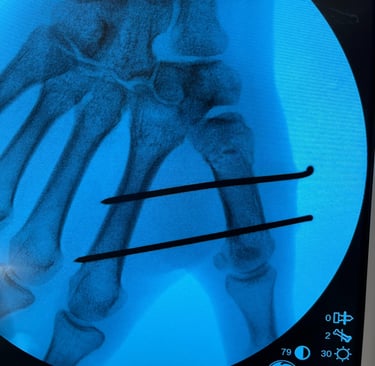

Polso e Mano

Mi occupo del trattamento delle principali patologie della mano e del polso, sia degenerative che traumatiche. Tratto condizioni frequenti come sindrome del tunnel carpale, dito a scatto, tendiniti e traumatologia della mano e del polso, con approccio conservativo o chirurgico mirato al recupero della funzionalità e alla riduzione del dolore.